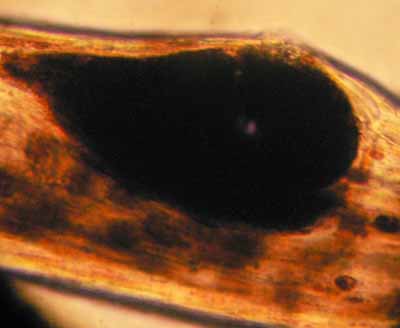

On trouve une anomalie de répartition de la mélanine à la base du poil ainsi que des mégamélanosomes (macromélanosomes) dans le poil en position sous cuticulaire fragilisant le poil comme dans l’alopécie des robes diluées.

Photo 12 DF : amas de mélanine à la base du poil

Photo 13 DF : mégamélanosome dans une tige pilaire